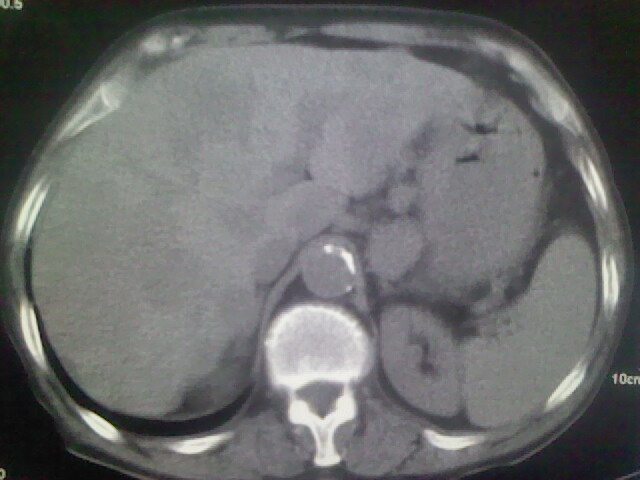

男,70y,胃占位,重度贫血,黑便3月余,伴恶心,纳差,乏力

胃癌,并肝,右肺,右径部,纵隔淋巴结转移

胃癌,并肝,右肺,右颈部,纵隔淋巴结转移

1)考虑右肺上叶周围型肺癌并纵隔及右颈部淋巴结转移,肝脏多发性转移。2)肺气肿。3)冠状动脉及主动脉钙化。

资料不清晰啊,肺内病灶内可见多发钙化影,结核不能除外.肝内符合转移瘤表现.既然楼主提供胃内占位,那原发灶还是考虑来源于胃腔.